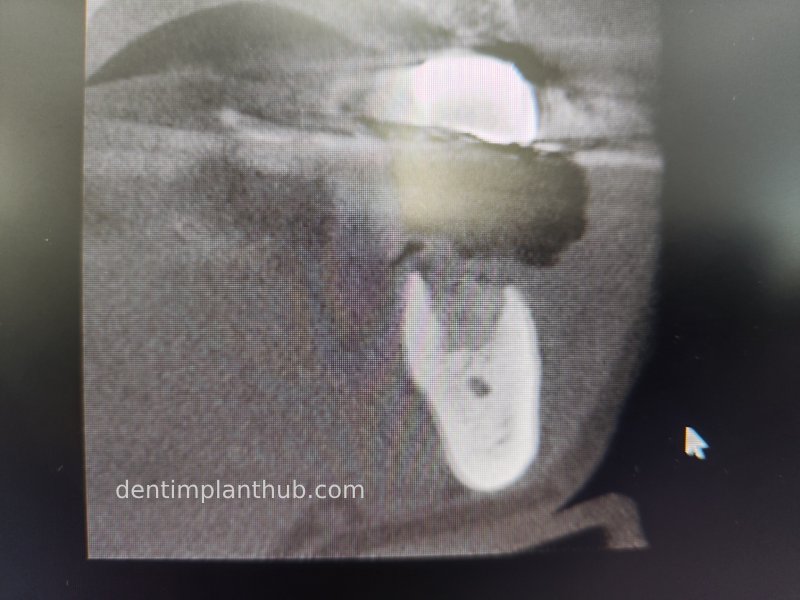

Post-surgical CBCT review photos

16

14

12

22

24

26